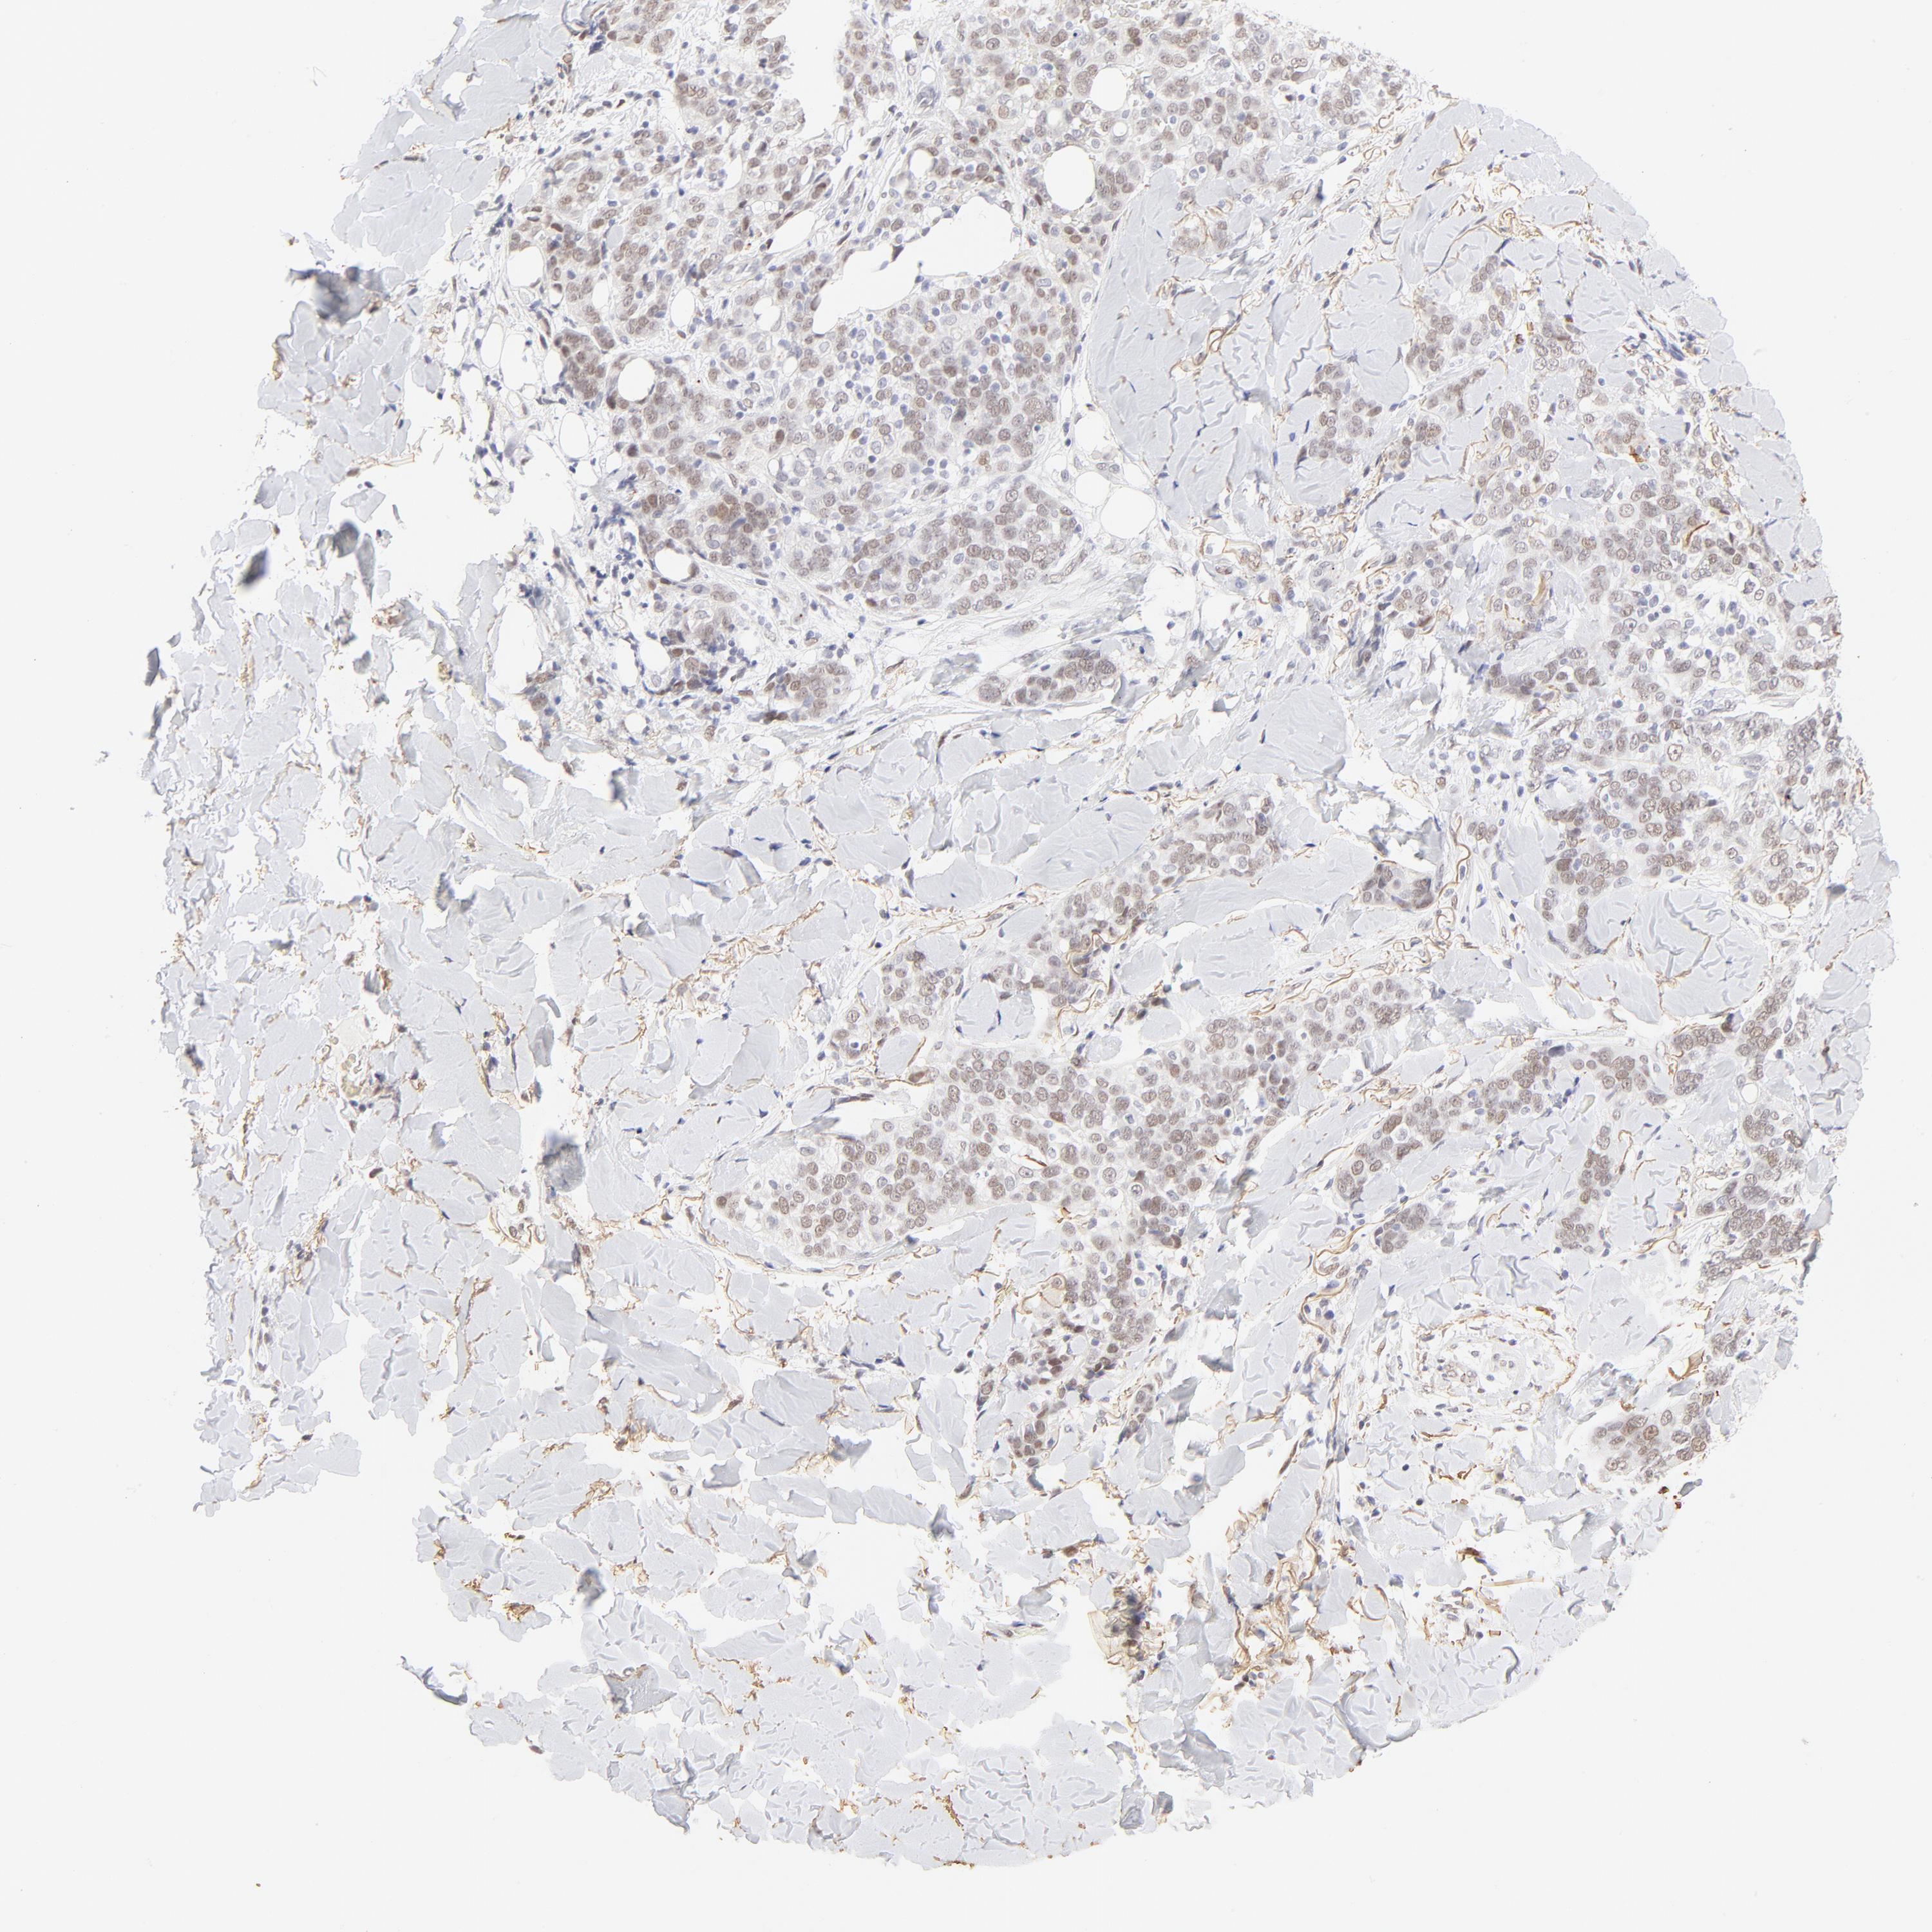

SKIN CANCER - Protein expressioni

A mouse-over function shows sample information and annotation data. Click on an image to view it in a full screen mode. Samples can be filtered based on level of antibody staining by selecting one or several of the following categories: high, medium, low and not detected. The assay and annotation is described here.

Each image is clickable and will lead to virtual microscopy that enables deeper exploration of all samples and also displays staining intensity scores, fraction scores and subcellular localization as well as patient and tissue information for each sample.

Antibody HPA003881

Staining

High

Medium

Low

Not detected

Intensity

Strong

Moderate

Weak

Negative

Quantity

>75%

75%-25%

<25%

None

Location

Nuclear

Cytoplasmic/membranous

Cytoplasmic/membranous,nuclear

Basal cell carcinoma